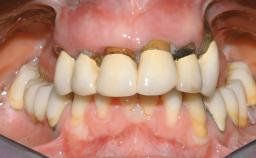

A 63-year-old male patient was referred for a consultation and treatment of partial edentulism in the maxilla. The patient presented with residual anterior teeth and declined a partial removable prosthesis. He reported that the maxillary posterior teeth had been extracted due to mobility and periodontal disease two months before the consultation. The patient’s chief complaint was that his residual maxillary teeth were mobile and that he was unable to chew. The patient’s desire was a stable and comfortable fixed maxillary rehabilitation. The patient was a light smoker (fewer than 10 cigarettes/ day), and his medical history was without significant findings. He was not on any regular medication at the time of consultation. The extraoral examination revealed a normal physiognomy with a correct distribution of the facial thirds. The patient presented a low lip line, and the transition line between teeth and soft tissues was not exposed during a forced smile.

Lip Line No exposure of papillae Exposure of papillae Full exposure of mucosa margin

Periodontal Phenotype Low-scalloped, thick Medium-scalloped, medium-thick High-scalloped, thin